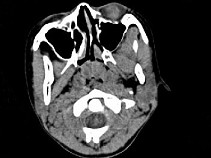

4.女,8岁,头痛,鼻塞半年余,CT如图所示,最可能诊断为 ( )![]() ![]() ![]() ![]() |

| 正确答案:C |